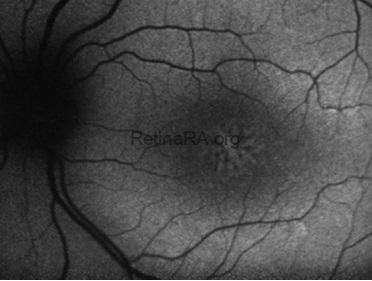

Fundus imaging revealed an abnormal foveal reflex with cystic lesions in both maculae. The right eye showed peripheral old laser scars and dome-shaped schisis, while the left eye demonstrated foveal schisis with a characteristic spoke-wheel pattern radiating from the fovea, along with an inferotemporal peripheral schisis.

Fundus autofluorescence of the left eye showed alternating hyper- and hypoautofluorescent areas corresponding to the spoke-wheel pattern.